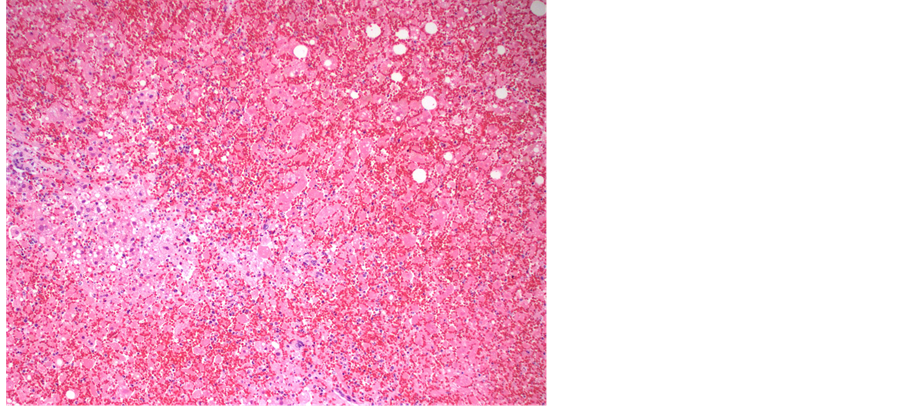

examined showed any signs of viral infection, inflammation or necrosis, including the central nervous system, gastrointestinal tract, larynx and trachea. Viral inclusions were presents and presence of HSV was confirmed with immunohistochemical stain. The liver was slightly enlarged (2128 grams, reference range, 1500 - 1800 grams), and had firm, dark red parenchyma. Microscopically, the liver parenchyma was diffusely necrotic (Fig- ure 1), with minimal cellular detail, and with abundant parenchymal hemorrhage. Many of the viable hepatocytes had enlarged, deeply basophilic nuclei with the characteristic “ground glass” chromatin pattern that in some instances resemble ground glass nuclear inclusions (Figure 2). Other nuclei had the characteristic punctate, granular chromatin pattern (Figure 3). Although the histologic features are quite characteristic of herpes virus infection, this was confirmed with an HSV immunohistochemical stain (Figure 4). These nuclear changes are commonly refered to as “viral cytopathic effect,” and were observed in essentially all sections of the liver examined.

Figure 1. Low power view of liver parenchyma composed predominantly of necrotic and diffusely hemorrrhagic tissue; a focal are of viable tissue is in the left aspect of the image (hematoxylin and eosin, 40× magnification).